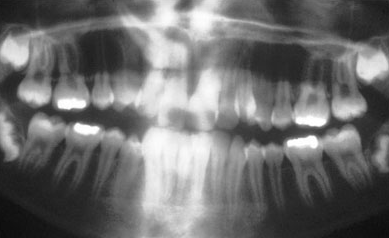

Unerupted incisors have several possible causes, these tend to be either [blank_start]hereditary[blank_end] or environmental in origin. Environmental causes include: 1. Trauma - [blank_start]avulsion[blank_end] or intrusion of the primary teeth that causes damage to the permanent tooth. This may include the root/crown axis to deviate, known as [blank_start]dilaceration[blank_end]. The permanent tooth may also become [blank_start]ankylosed[blank_end] to the bone. In these cases [blank_start]extraction[blank_end] may be required and tooth replacement options considered. 2. [blank_start]Retained[blank_end] primary teeth causing [blank_start]delayed[blank_end] eruption - this may cause a physical [blank_start]obstruction[blank_end] to the path of eruption of the permanent tooth. The most straightforward option here would be [blank_start]extraction[blank_end] of the primary tooth if there is no other obstruction and the teeth are close to [blank_start]eruption[blank_end]. Hereditary causes may include the presence of [blank_start]supernumerary[blank_end] teeth in the arch, [blank_start]cleft[blank_end] lip or palate, abnormal tooth/tissue ratio or other rarer conditions such as [blank_start]cleidocranial[blank_end] dysostosis. The other option is that the permanent teeth may be congenitally [blank_start]absent[blank_end]! According to the RCS guidelines, we should start monitoring unerupted incisors when: 1. [blank_start]Contralateral[blank_end] teeth erupted more than 6 months ago 2. Both centrals are unerupted and the lowers erupted more than [blank_start]12[blank_end] months ago 3. Deviation in the normal sequence of eruption During an intra oral examination, you may find that: - The primary teeth have been retained beyond normal [blank_start]exfoliation[blank_end] dates (which is [blank_start]6[blank_end] or [blank_start]7[blank_end] years for upper centrals, [blank_start]7[blank_end] or [blank_start]8[blank_end] years for upper laterals) - There may be buccal or palatal [blank_start]swellings[blank_end] on palpation - Note the space available for incisors - [blank_start]9[blank_end]mm for centrals and [blank_start]7[blank_end]mm for laterals You may wish to take some [blank_start]radiographs[blank_end] to determine the cause of the unerupted teeth. The [blank_start]parallax[blank_end] technique can locate the position of impacted teeth.

• radiographs

• parallax

The upper canines usually erupt around [blank_start]11[blank_end] or [blank_start]12[blank_end] years of age. [blank_start]Congenitally[blank_end] absent canines is rare 0.3%. [blank_start]Impaction[blank_end] of canines is more common, and is usually bilateral. You should be able to [blank_start]palpate[blank_end] maxillary canines around 9 years of age in the buccal [blank_start]sulcus[blank_end]. Causes of impacted maxillary canines may be due to the: - [blank_start]Long[blank_end] path of eruption - [blank_start]Short[blank_end] rooted or [blank_start]absent[blank_end] upper lateral incisors ([blank_start]peg[blank_end] laterals) - Crowding - [blank_start]Retention[blank_end] of primary canine (an indicator rather than a cause!) - [blank_start]Genetic[blank_end] factors. It may run in the [blank_start]family[blank_end]. - It should also be noted that impacted canines is associated with other dental anomolies You should first assess the child [blank_start]clinically[blank_end] to see if you can tell where the tooth is displaced. If you suspect displacement you may wish to take some [blank_start]radiographs[blank_end]. The radiographs most commonly used for assessing ectopic canines are [blank_start]panoramic[blank_end] radiographs, upper [blank_start]occlusal[blank_end] radiographs, lateral [blank_start]cephalometric[blank_end] (for more accurate localisation), [blank_start]cone beam[blank_end] computerised tomography, and periodicals (useful for prognosis of retained deciduous canines). Management depends on wether the teeth are [blank_start]buccally[blank_end] or [blank_start]palatally[blank_end] displaced. Buccal displacements are usually due to [blank_start]crowding[blank_end], so relief of [blank_start]crowding[blank_end] is usually the option Palatal displacements may require surgical [blank_start]exposure[blank_end] with orthodontic [blank_start]alignment[blank_end], or surgical [blank_start]removal[blank_end] of the impacted canine. Occasionally unerupted canines can cause [blank_start]resorption[blank_end] of adjacent lateral incisor roots and possibly the centrals. In this case intervention should be done swiftly.

• panoramic

• occlusal